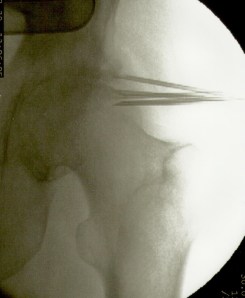

La artroplastia total de cadera para los casos de coxartrosis severa es el tratamiento de elección de la gran mayoría de cirujanos ortopédicos. Sin embargo cuando el paciente es menor de 50 años suele diferirse la intervención debido al tiempo de sobrevida del material protésico. También lo es en pacientes con deterioro del estado general debido a la avanzada edad o a enfermedades concomitantes (cardiópatas, por ej.) En estos casos la colocación de microimplantes de oro periarticulares alrededor del cuadrante súpero externo de la articulación es, habida cuenta del resultado sintomático y funcional, el tratamiento más indicado. La fácil colocación mediante control radioscópico y la rapidez de la recuperación (inmediata) hacen que este procedimiento sea seguro y muy útil para la remisión del dolor y la rigidez. No necesita ingreso ya que es una cirugía ambulatoria, se efectúa con anestesia local, y el paciente sólo requiere reposo relativo en el día de la intervención. Los resultados mediatos son excelentes. La mejoría clínica aumenta con los meses debido a la difusión de las nanopartículas de oro, por lo que contrariamente a los tratamientos convencionales que disminuyen su efecto con el tiempo, los microimplantes de oro lo mejoran. En cuanto esta técnica se popularice se reducirá significativamente el número de artroplastias.

Más abajo se observarán unas imágenes de casos de implantes de oro en cadera